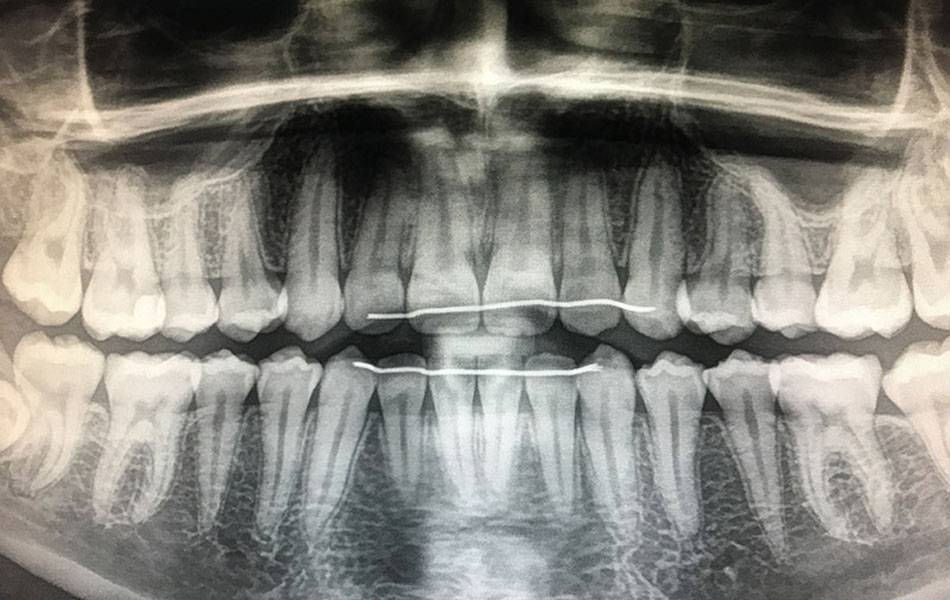

Digitales Röntgen

In der modernen Zahnmedizin ist das Röntgen ein elementarer Bestandteil, wenn es darum geht, die Zahngesundheit des Patienten festzustellen. Mit dieser Technik ist es möglich, den Bereich zwischen den Zähnen einzusehen, sowie den Zustand im Inneren eines Zahnes und seine Wurzeln im Kieferknochen zu untersuchen.

Dieses bewährte Verfahren haben wir in unserer Praxis auf den neuesten Stand der Technik gebracht: Bei uns findet nun das digitale Röntgen Anwendung. Die Vorteile für uns als Mediziner, aber auch für Sie als Patienten sind dabei deutlich spürbar: Die Qualität und Handhabung der Aufnahmen ist besser und einfacher. Die Bilder stehen unmittelbar nach der Aufnahme am Computer zur Verfügung. So lassen sich Bereiche gezielt vergrößern und bewerten, der Kontrast ist zu justieren, was eine bessere Bildqualität mit sich bringt und wir so den Beschwerden noch genauer auf den Zahn fühlen können. Vor allem aber wird die Strahlenbelastung, der sie beim Röntgen ausgesetzt sind, mit diesem modernen Verfahren um rund 90% reduziert.

Wir freuen uns, dass wir Ihnen diese Neuerung für Ihre Zahngesundheit anbieten können. Wenn Sie Fragen zum digitalen Röntgen haben, stehen wir Ihnen gerne zur Verfügung.